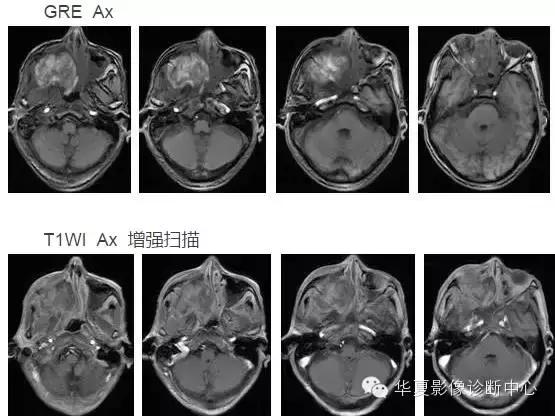

中枢神经系统内原发性黑色素瘤少见, 因脑和脊髓的软脑( 脊) 膜及蛛网膜上含有黑色素细胞, 黑色素可发生于软脑( 脊) 膜的任何部位,故其发生部位常位于脑( 脊髓) 表面, 沿软脑膜生长; 而继发性黑色素瘤同一般转移性肿瘤, 常位于灰白质交界区。

影像表现:常表现为短 T1 高信号, 短T2WI 低信号,又因为黑色素瘤是富血管性肿瘤, 增强扫描常表现为明显强化。

依据黑色素瘤的不同 MRI 影像表现将其分为 4 种类型: ( 1) 黑色素型。该黑色素瘤因含有丰富的黑色素颗粒, MRI表现较典型,即短 T1 高信号,短 T2 低信号。( 2) 无黑色素型。因该类黑色素瘤不含黑色素颗粒或含量较低,MRI 表现为长 T1 低信号,长 T2 高信号; ( 3) 混合型。黑色素型和非黑色素型两者的混合; ( 4) 出血型。表现为血肿不同时期的信号特征, 该黑色素瘤 MRI增强扫描表现为不均匀环状或弥漫性强化